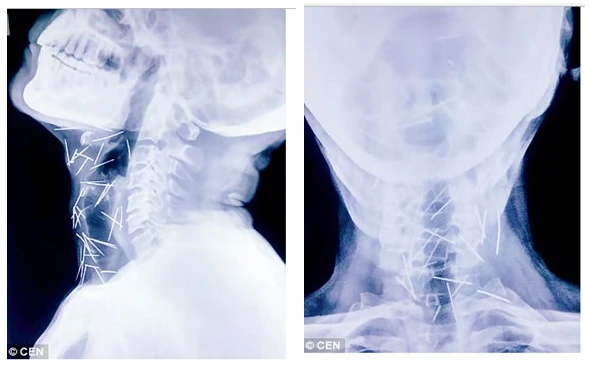

Ảnh chụp X-quang cho thấy kim nằm trong cổ bệnh nhân. Ảnh: DAILY MAIL

Sau khi tiếp tục kiểm tra, các bác sĩ phát hiện có tới 75 cây kim trong cơ thể ông Meena. Trong số 75 cây kim, có 40 cây nằm trong cổ họng, 25 cây ở chân và 2 cây ở cánh tay.